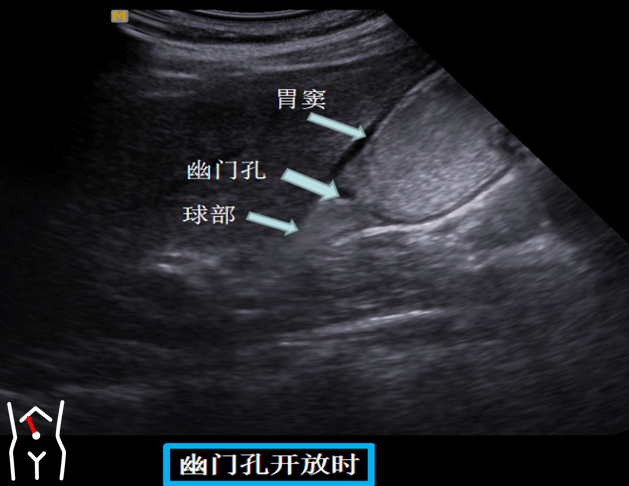

第四组胃窦球部切面

患者从右卧位改成平卧此时头也随着患者改变体位而由横切改为纵切在脐孔与右肋缘连线处扫出胃窦幽门管幽门孔球部降部水平部